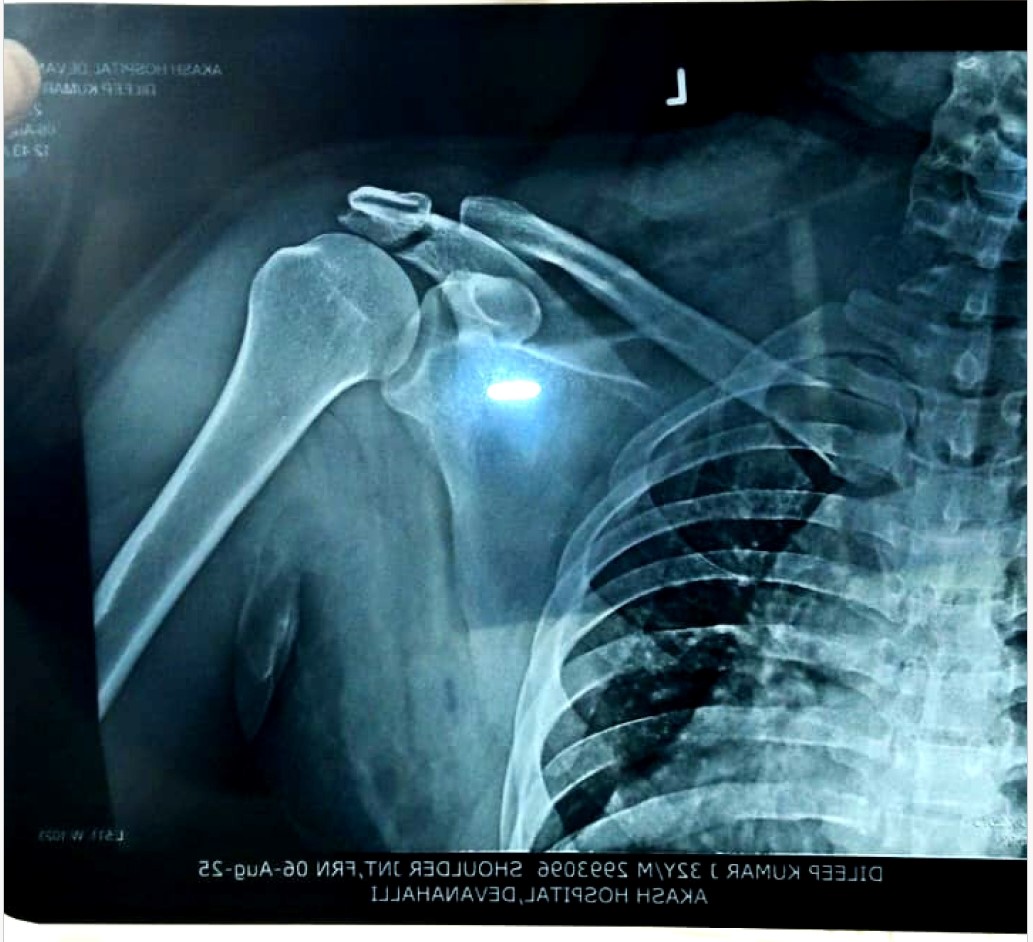

Dileep J, a 31-year-old young man, met with a devastating road traffic accident (RTA) that left him with severe trauma to his left brachial plexus. This injury has led to complete motor loss (0/5) and sensory loss across multiple nerve levels (C5 to T1), affecting his ability to use his arm and shoulder. MRI and CT reports reveal extensive damage, including thickened nerve trunks, fluid accumulation, and edema in both superficial and deep tissues of the neck and chest.

Despite the severity, his spinal cord remains intact, giving hope for recovery if prompt medical intervention is provided. Doctors have recommended further treatment and a follow-up scan after three months to assess nerve healing and potential for surgical repair or advanced therapy.